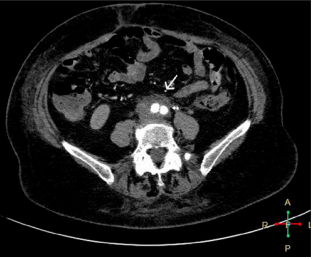

The patient's laboratory values improved notably and a new MDCT of the abdomen and pelvis with intravenous contrast was performed 3 months after hospital discharge, where the retroperitoneal image described above was no longer evident (Figure 3 and 4).1-8

Figure 3 MDCT with intravenous contrast, arterial phase, axial view. There is evidence of free retroperitoneum without formation, aorta with contrast.